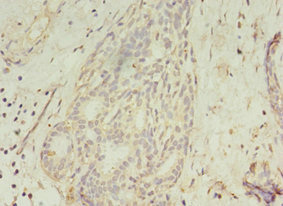

Immunohistochemistry of paraffin-embedded human colon cancer using CSB-PA846598LA01HU at dilution of 1:100

CSB-PA846598LA01HU

Immunohistochemistry of paraffin-embedded human breast cancer using CSB-PA846598LA01HU at dilution of 1:100